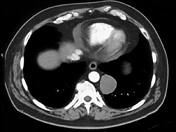

男,33岁,背部不适,无发热,结合CT图像,选择最可能的诊断是 ( )A.椎旁脓肿B.神经源性肿瘤C.脑脊膜膨出D.食管囊肿E.淋巴瘤

问题 男,33岁,背部不适,无发热,结合CT图像,选择最可能的诊断是 ( )

选项 A.椎旁脓肿 B.神经源性肿瘤 C.脑脊膜膨出 D.食管囊肿 E.淋巴瘤

答案 B